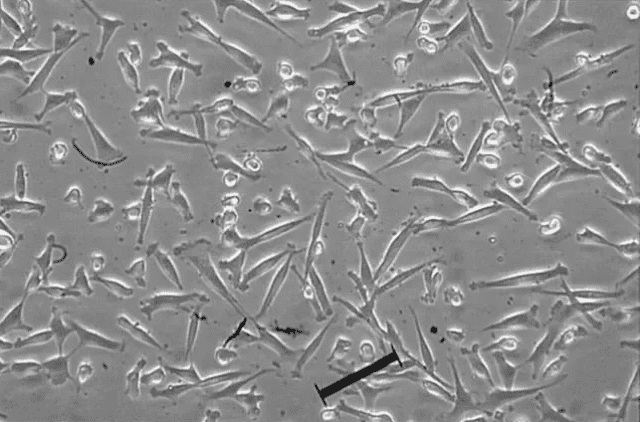

伴隨著2010年英國FDA準許DC細胞變成癌癥治療的新方式,2011年諾貝爾獎醫學獎落花免疫細胞醫治,對于腫瘤的免疫細胞醫治技術性發展趨勢邁入了豐收的季節,它將變成傳統式醫治方式以外最具使用價值和發展···

隨著人們對醫療保健意識的日益增強,間充質干細胞等干細胞概念已通過各種宣傳渠道引起公眾的關注。截至2022年3月,已有1400多項間充質干細胞臨床試驗在Clinical Trials中注冊。其中,我國進···

認識CAR-T療法CAR-T療法就是嵌合抗原受體T細胞免疫療法,英文全稱Chimeric Antigen Receptor T-Cell Immunotherapy。這是一種治療腫瘤的新型精準靶向療法···